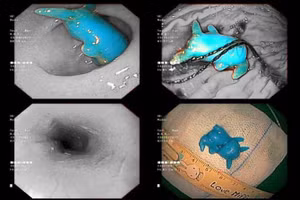

Gắp dị vật là mảnh lego 5cm trong dạ dày bé 33 tháng tuổi

GD&TĐ - Bệnh viện Trẻ em Hải Phòng mới tiếp nhận trẻ 33 tháng tuổi, sau thăm khám, các bác sĩ xác định trẻ nuốt phải dị vật là mảnh lego.